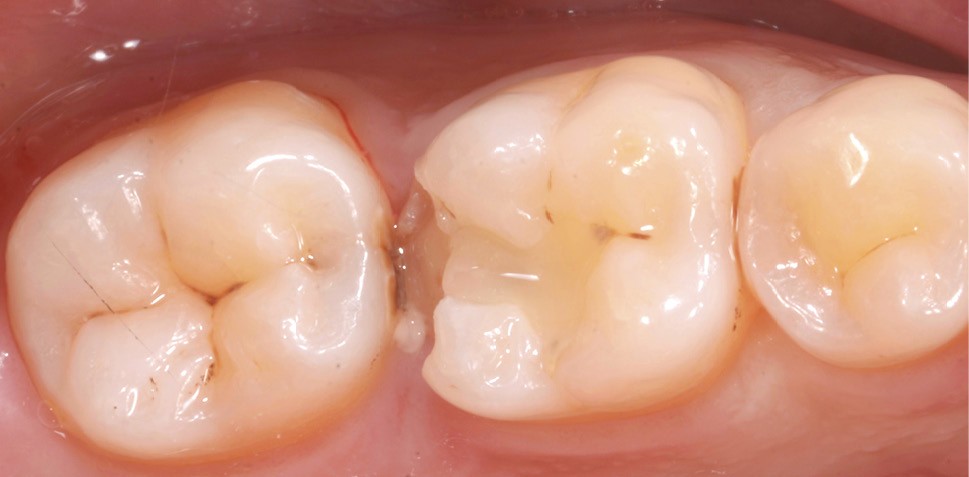

Lors de la préparation d’une cavité pour inlay/onlay, il est fréquent d’être confronté, en fin de nettoyage, à la présence d’une ou plusieurs parois résiduelles dont la résistance mécanique paraît douteuse du fait de leur localisation ou de leur épaisseur. Les parois épaisses (+ de 2 mm) peuvent généralement être conservées (cas clinique 1) et les parois fines (- de 1 mm) doivent généralement être recouvertes. Un inlay (en composite ou en céramique) est alors réalisé. Il doit avoir lui même, au final, une épaisseur globale minimale de 2 mm pour assurer sa résistance mécanique intrinsèque à la mastication. Si un recouvrement cuspidien est indiqué, la réduction occlusale doit donc se faire sur 2 mm de hauteur au minimum [1, 2].

Mais qu’en est-il des parois résiduelles d’épaisseur intermédiaire (entre 1 et 2 mm) (cas clinique 2) ?

La localisation (type de dent)

Le pronostic clinique semble plus favorable pour les prémolaires que pour les molaires [3-5], car une plus grande résistance est généralement nécessaire pour les parois des molaires. Mais si 75 % des fractures à la mandibule affectent les molaires, et plus particulièrement la première molaire, au maxillaire, les fractures se répartissent équitablement entre le secteur molaire et le secteur prémolaire [6]. L’épaisseur de l’émail, la largeur de la cuspide comme les…